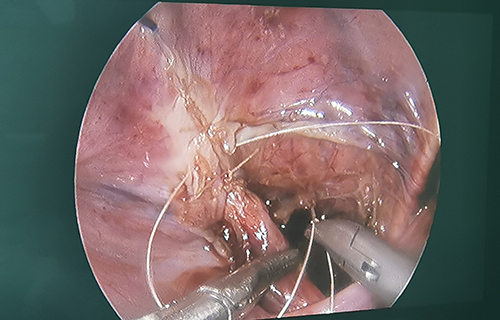

术前准备完毕。10月15日,栾志勇主任、谢方达副主任为佳佳行输尿管远端狭窄微创手术,在其肚脐周围打了3个直径5mm的小孔,在腹腔镜下顺利实施了输尿管膀胱再植。手术用时仅为3小时,出血量也比较少。

“如果开刀手术,需要在腹部做横切口,对孩子的损伤是比较大的。在保证手术效果的基础上,微创手术对孩子的损伤小,美观程度良好,术后恢复比较快。”栾志勇主任说。